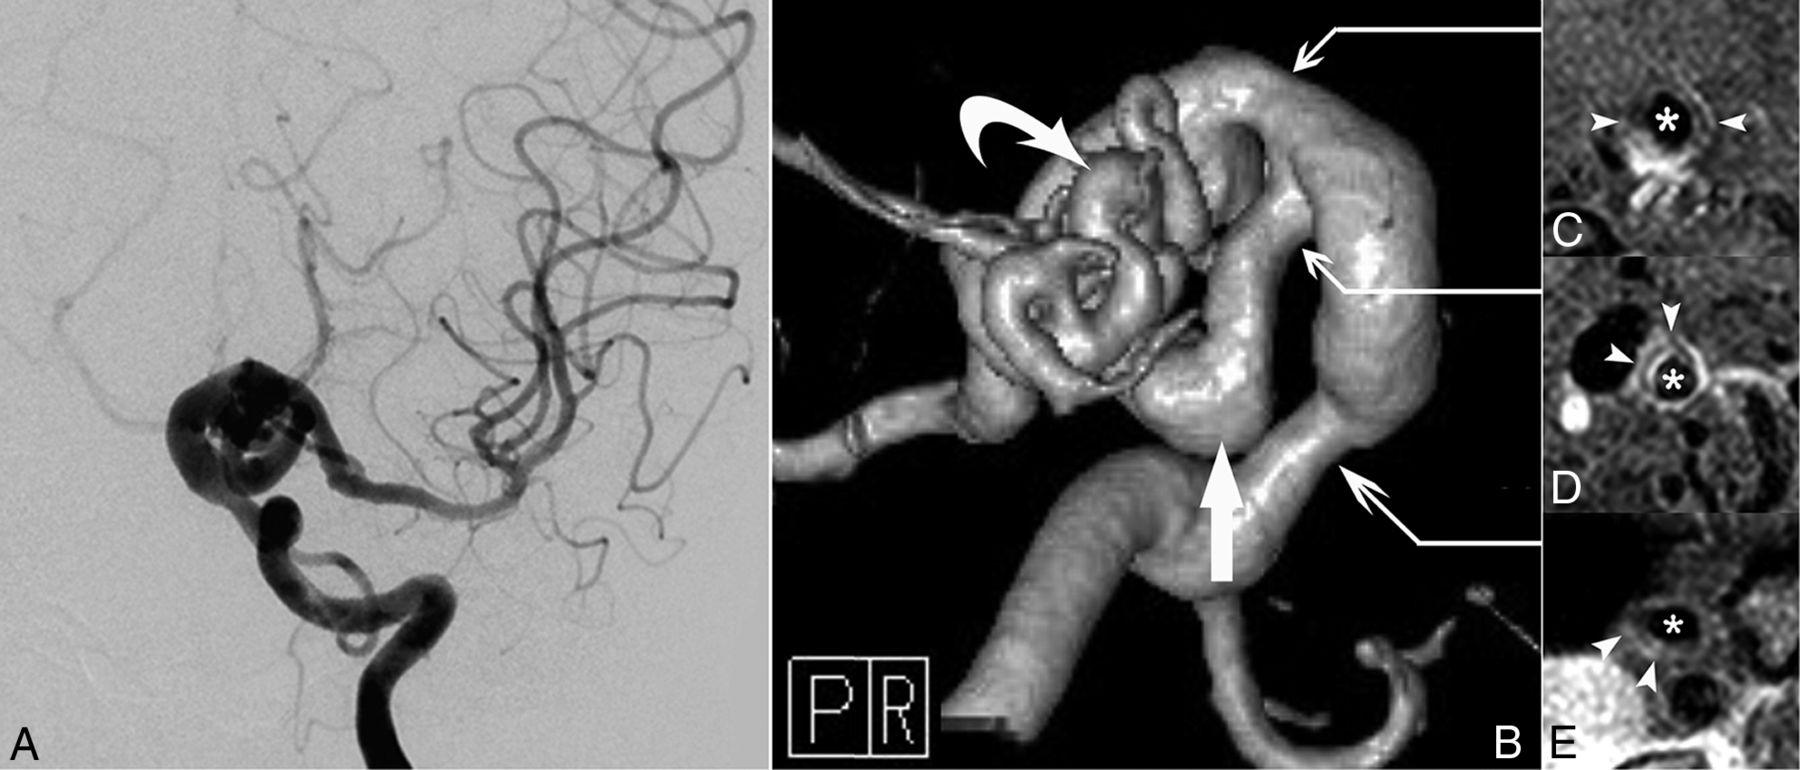

Vessel wall enhancement at the stenotic segment in a patient with possible PHACE syndrome (patient 5, a 23-year-old woman). A and B, Left ICA angiography and TOF-MRA reveal dolichoectasia of the left distal ICA, left PcomA (arrow), and left AchoA (curved arrow). C–E, Section images reveal the vessel wall thickening and enhancing patterns of each corresponding stenotic segment (arrowheads indicate the vessel wall thickening and asterisks indicate vessel lumen; C, sagittal plane; D and E, axial plane). P indicates posterior; R, right.